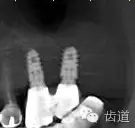

2、45,46術(shù)前片顯示根管上段充填物,根管影像不清晰,少許根尖暗影